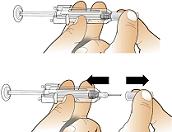

How to prepare the Aranesp injection (pre-filled syringe)

Before you inject Aranesp you must do the following:

Gently pull the needle cover from the needle. Do not touch the needle or plunger.

Hold the syringe with the needle pointing up to see if it has any air bubbles inside. If there are, gently press the plunger

until all the air (but none of the liquid) has been removed.

You can now use the pre-filled syringe.